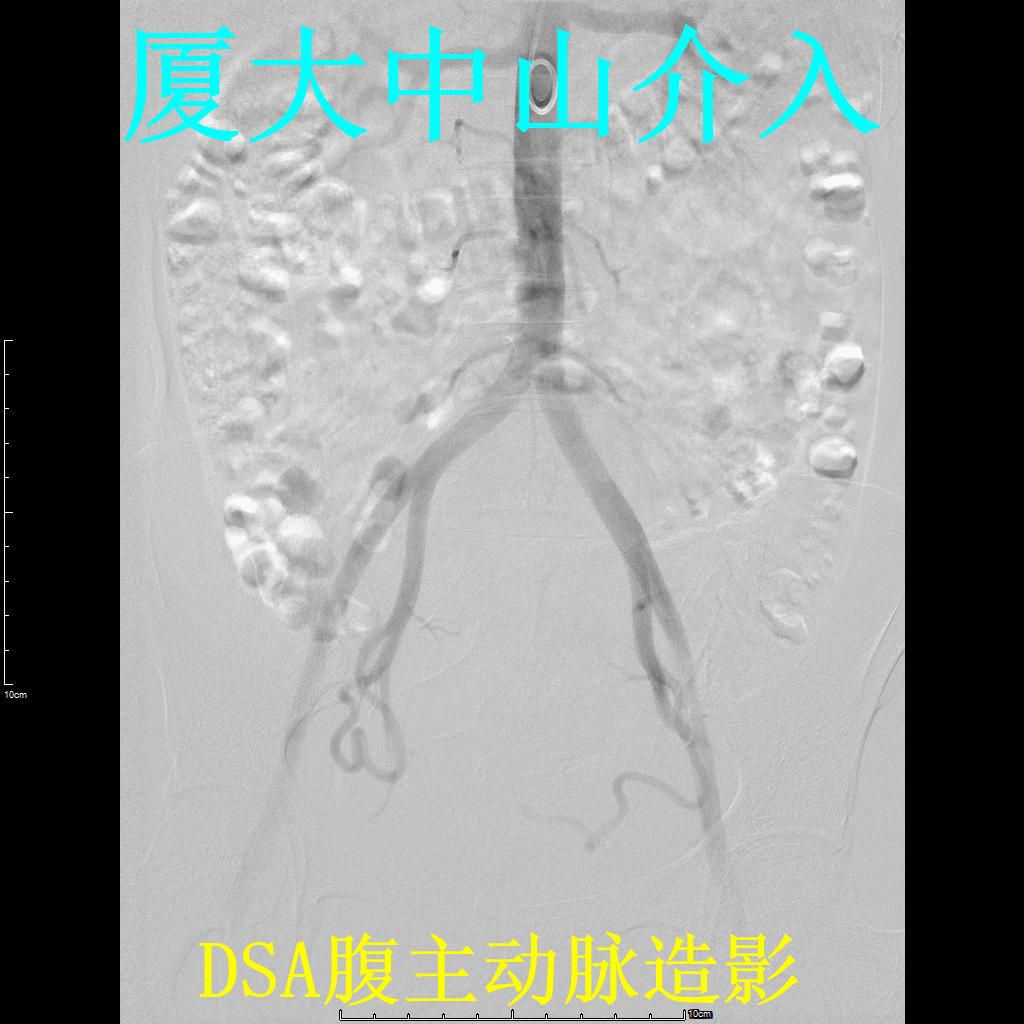

经桡动脉穿刺插管造影

左侧子宫动脉造影+栓塞

右侧子宫动脉造影+栓塞